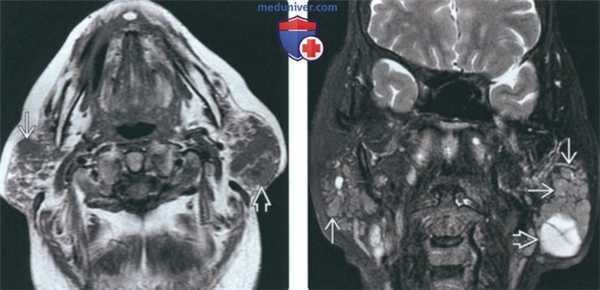

(Слева) МРТ Т1ВИ, аксиальная проекция. Увеличенные околоушные железы с неоднородной структурой. У пациента, которому 10 лет назад был выставлен диагноз синдрома Шегрена, появилось пальпируемое образование в левой околоушной области. Лечащий врач обнаружил образование и с правой стороны.

(Справа) МРТ Т2ВИ FS, коронарная проекция. В обеих околоушных железах обнаруживаются множественные образования с сигналом промежуточной интенсивности, слева также имеются солидные и кистозные структуры. После проведения аспирационной биопсии был выставлен диагноз MALT-лимфомы с обеих сторон. Пациенту был проведен курс лучевой терапии.

(Слева) На аксиальной МРТ (Т1 ВИ) определяется выраженное увеличение околоушных желез, имеющих неоднородную структуру. У пациента 10 лет страдающего болезнью Шегрена, обнаружена пальпируемая опухоль левой околоушной железы, справа в железе обнаруживается узел, определяющийся также клинически.

(Справа) На корональной MPT (Т2 ВИ FS) у этого же пациента с обеих сторон определяются множественные очаги промежуточным сигналом, а также кистозно-солидная опухоль слева вв При исследовании аспирата из очагов с обеих сторон подтвердилась MALT-лимфома. Была назначена лучевая терапия.